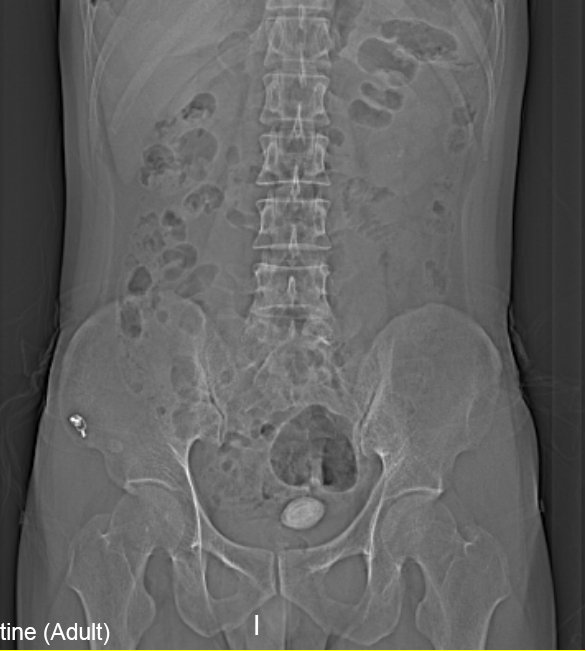

“醫生我尿不出,尿里有血,快幫幫我”。近日,在溫州市人民醫院泌尿外科門診一位男青年向坐診的黃來劍主任求助,經驗豐富的黃主任在了解基本病情后,特意觸摸了一下患者恥骨上區,并囑咐患者進行泌尿系平片檢查,結果在意料之中也出乎意料之外。意料之中的是患者診斷如黃主任所想膀胱結石進入尿道卡住了,意料之外的是結石直徑達到了35mm,像蛋黃大小了,這對年輕患者來說并不常見,堵住了尿道,把患者痛的夠嗆。

▲患者影像學檢查